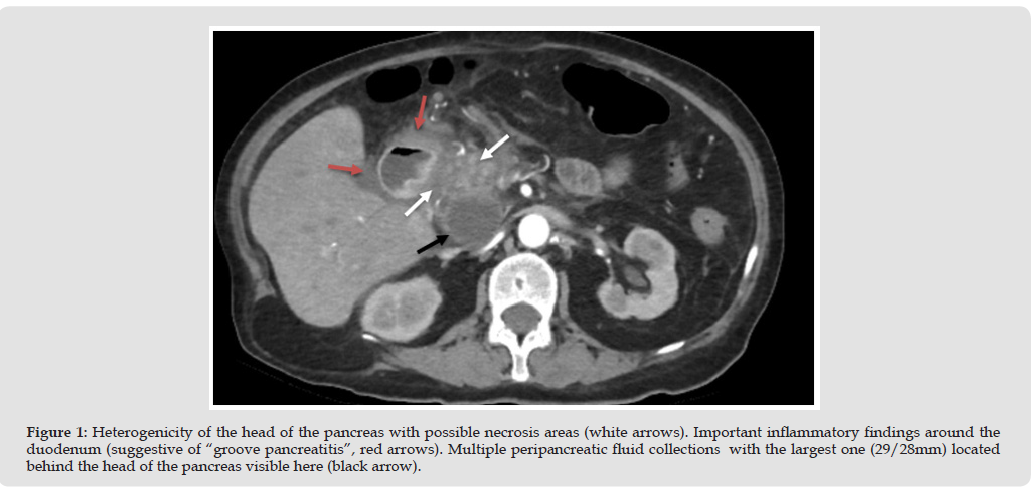

A 68 y.o. woman is admitted to the gastroenterology ward presenting with upper abdominal pain and shortness of breath. The patient is non-smoker, declares no alcohol consumption, personal history includes hypertension, cholecystectomy and multiple surgeries for recurrent kidney stones. She is tachycardic, BP 140/70mmHg, whole abdomen is tender and painful with the epigastric region being the most sensitive, slower bowel movements (1-3 days between stools), no stool abnormalities. No significant changes in ECG, blood tests show hyperamylasemia (2x ULN), hyperlipasemia (3x ULN), renal failure (BUN/Creatinine ratio > 20), hypercalcemia (11.9 mg/dL), hyperuricemia, hypokalemia, high alkaline phosphatase, normocytic, normochromic anemia. Abdominal ultrasound shows hyperechoic pancreas with a 30/20mm non-homogenous structure located near the head of the pancreas, no pancreatic ducts dilations, no intrahepatic or extrahepatic bile ducts dilation, no gallstones visible, no signs of hydronephrosis or kidney stones. Acute pancreatitis is the most probable diagnosis with a possible pancreatic tumor located next to the head of the pancreas. Treatment is started with a poor response, no clinical improvement over the next days with worsening laboratory findings (rising amylase and lipase levels). Abdominal CT scan is used for better evaluation, no pancreatic tumor is found, severe acute pancreatitis is present, most affected being the head of the pancreas, pseudocysts are present with partial acute splenic vein thrombosis.

No bile duct obstruction is found, ruling out this as a possible cause of acute pancreatitis, however slight dilation of intrahepatic bile ducts and main bile duct is present, duodenal inflammation being the most probable cause of this. Final description of CT scan suggests a chronic pancreatitis with a severe acute episode, judging by the more localized aspect of the inflammation (head and duodenum) with slight atrophy of the body and tail of the pancreas, 8 points on the Modified Computed Tomography Severity Index (mCTSI [5], (Figures 1 & 2)). All findings suggest a severe necrotising pancreatitis (in accordance with Revised Atlanta Criteria [6]) with acute necrotic collections present. Endocrinology recommends testing PTH levels which come back 20x upper limit of normal, which points to primary hyperparathyroidism being the cause of the hypercalcemia. Additional imaging is done. Thyroid ultrasound shows hypoechoic structure in the vicinity of the lower left parathyroid. Cervical CT scan shows nodular lesion located next to the lower left parathyroid gland (Figure 3). Whole body bone scintigraphy shows no bone lesions suggestive of tumors or metastases but shows hyperostosis of the frontal and parietal bones, secondary to primary hyperparathyroidism. A single dose of bisphosphonate (Zolendronic acid) is administered in an attempt to lower calcium levels and remove the precipitating factor causing severe acute pancreatitis. No change in calcium is observed over the following days but creatinine and BUN slowly increase.